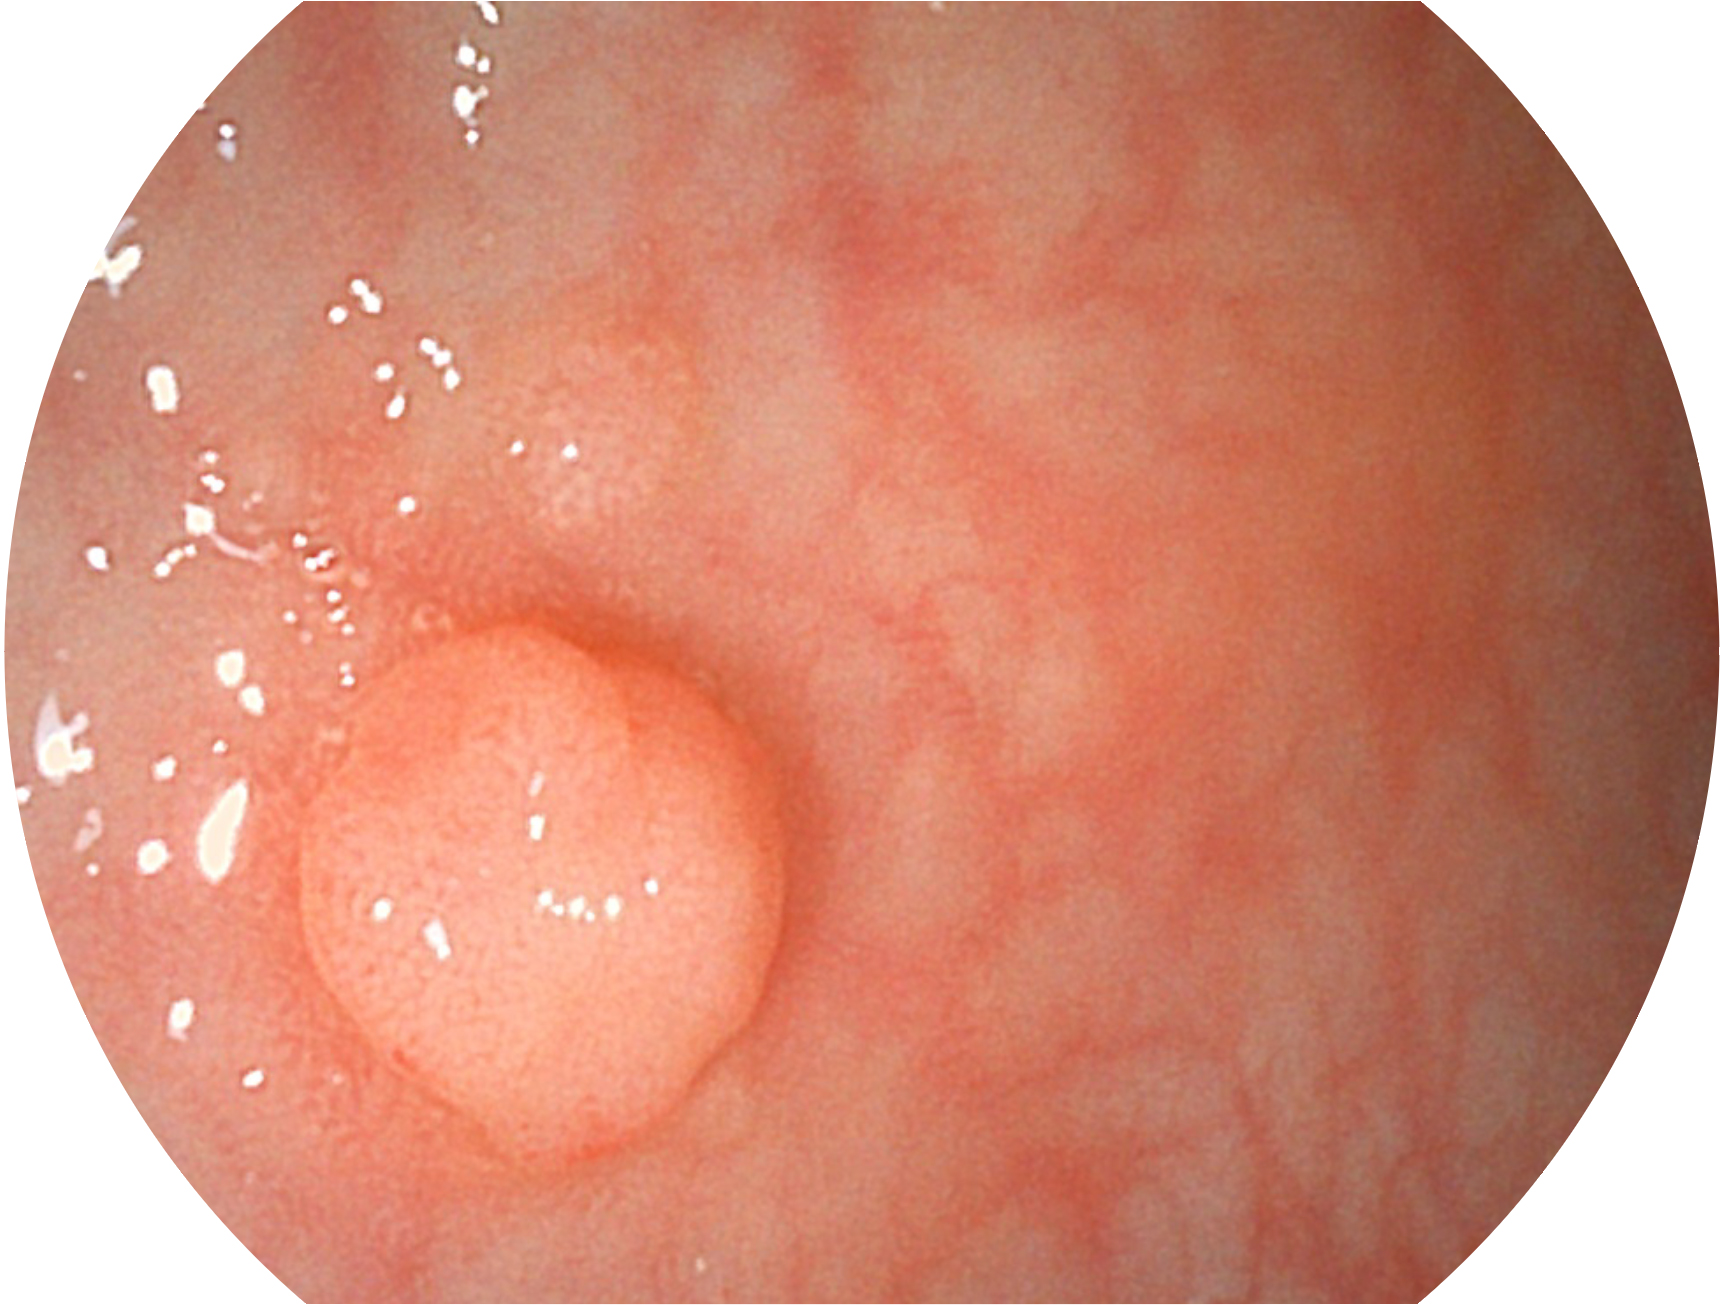

狗万官方网站新开发的内镜染色技术,主要是基于多波长LED 光源的开发,VLS-55Q 四波长LED 光源是由四个不同颜色的LED光按照相应照明模式所规定的特定发光比例进行合束后形成,合束后形成的照明光的光谱由红光、绿光、蓝光及蓝紫光这四个不同的波段范围构成。具有更高光谱自由度,通过光谱比例的控制,实现了聚谱成像技术,英文全称为“Spectral Focused Imaging, SFI”,缩写为“SFI”和光电复合染色成像技术,英文全称为“Versatile Intelligent Staining Technology, VIST”,缩写为“VIST”。